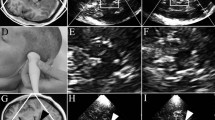

The brainstem, basal ganglia, and ventricles are imaged at standardised axial scanning planes, described in details in previous reviews [9] (Fig. 1).

Most important scanning planes and structures in the assessment of movement disorders in a healthy adult. a With the probe placed to the posterior or middle temporal bone, the mesencephalic plane parallel to the orbitomeatal line and the third ventricular plane obtained by tilting the probe 10–20° upwards are visualised. b Axial TCS image of the mesencephalic plane. The butterfly-shaped hypoechogenic brain stem (dotted line) is surrounded by echogenic basal cisterns. Within the brain stem, the slightly echogenic substantia nigra and part of the slightly echogenic round-shaped red nucleus is delineated, which is found closer to the midline. The midline raphe is shown as a continuous echogenic structure (arrow) dividing the brain stem into two parts. c Slightly oblique third ventricular plane: the contralateral skull is well visualised due to its hyperechogenicity. The frontal horns of the lateral ventricles and the hypoechogenic thalami are illustrated by dotted lines. The parallel echogenic borders of the third ventricle can be seen between the thalami. The normoechogenic nucleus lentiformis and the slightly echogenic nucleus caudatus are also depicted (echogenicity of these structures is determined contralateral to the probe). The calcificated pineal gland (white arrow), which is a landmark for orientation, and the calcificated choroid plexus of the lateral ventricle (arrow head) are marked. NC nucleus caudatus, NL nucleus lentiformis, T thalamus

Grading is based on the estimation of the sonographer when comparing SN echogenicity with the surrounding midbrain: in this semiquantitative approach, the SN is classified as either isoechogenic, mildly echogenic or hyperechogenic compared to the hypoechogenic brainstem. Of note, not only brightness but also size of the SN is incorporated in this rating. To better delineate adjacent structures (like the red nucleus), the rating should be performed after freezing of the image and a 2- to 4-fold magnification. This magnification is also necessary for the second approach: exact quantitative measurement of the small structure of the SN. In the frozen, magnified image, the ipsilateral SN is then traced manually and measured (SN planimetry in cm2) (Fig. 2).

TCS findings in healthy individuals and movement disorders. Zoomed images of the brain stem in a a control person and in a b PD patient. a Ipsilateral substantia nigra with normal size and echogenicity lateral of the round-shaped, partly visible red nucleus (dotted lines). b Ipsilateral substantia nigra with larger area of echogenicity and slightly increased brightness. c TCS image of the third ventricular plane in a patient with enlarged ventricular system. Enlarged frontal horn measured contralateral to the insonating probe perpendicularly from the septum pellucidum to the tip of the anterior horn and of the third ventricle measured between the ependymal layers as shown by the arrows. d Contralateral (large arrow) and ipsilateral (narrow arrow) hyperechogenicity of nucleus lentiformis (arrow). T thalamus (here lower part)